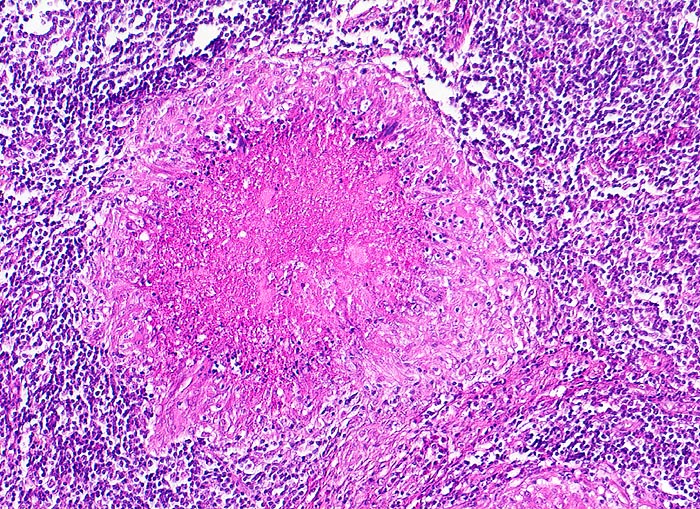

Basel 3BA HS/ Verkäsende Lymphknotentuberkulose

Verkäsende Lymphknotentuberkulose

• Lymphknoten mit ausgedehnten konfluierenden eosinophilen Nekrosezonen und nur wenig erhaltenem Lymphknotengewebe (blau).

• In den grösseren Nekrosearealen sind Kerntrümmer von neutrophilen Granulozyten erkennbar.

• Demarkierung der Nekroseareale durch schlanke Epitheloidzellen, Riesenzellen vom Langhanstyp mit hufeisenförmig angeordneten Kernen und Lymphozyten.